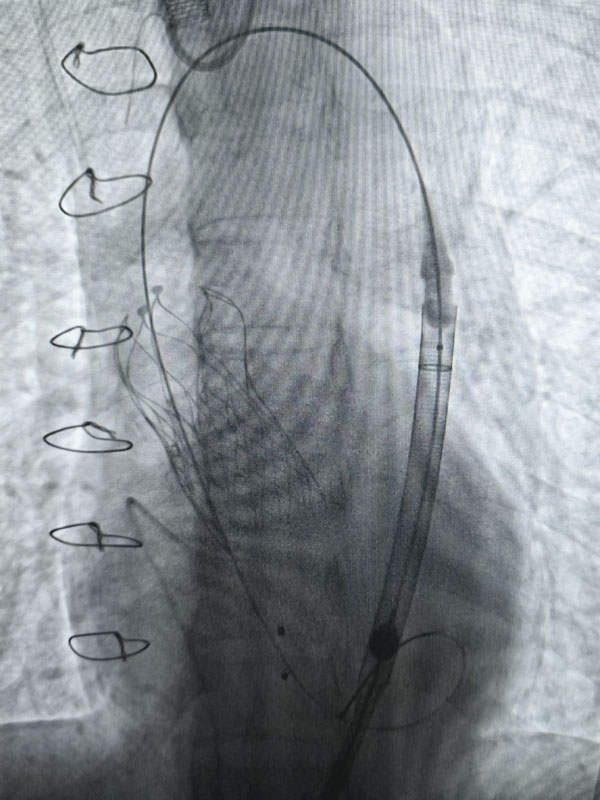

经过充分的术前准备,两台手术由心血管外科赵永波副主任主刀,赵伟超主治医师、侯五辉主治医师密切配合,选择经皮股动脉穿刺,预埋缝合器,术中反复造影,准确定位释放瓣膜,术后造影及超声提示人工瓣膜开启功能良好。为确保术中安全,体外循环小组全程保驾护航。患者生命体征平稳,术后一日均转出监护室。